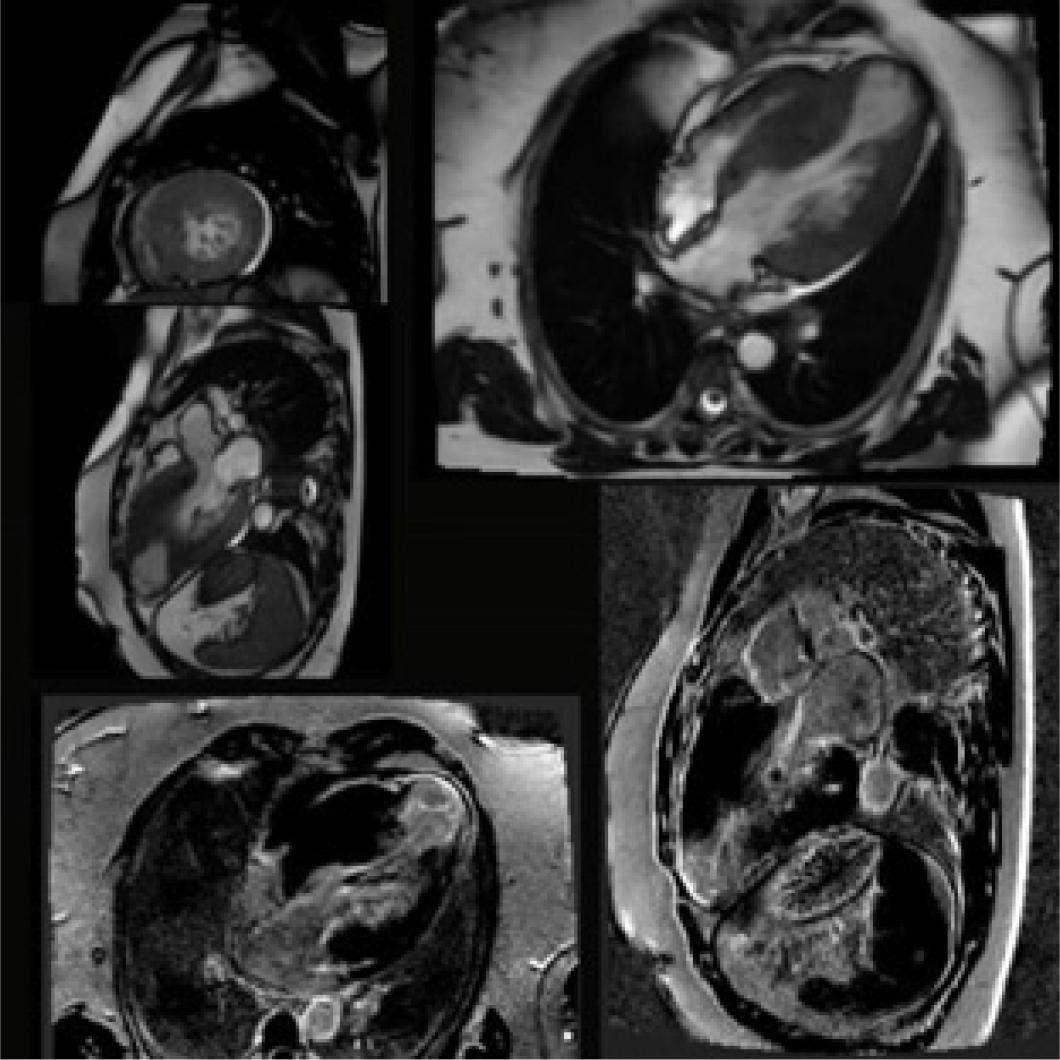

Figure 1